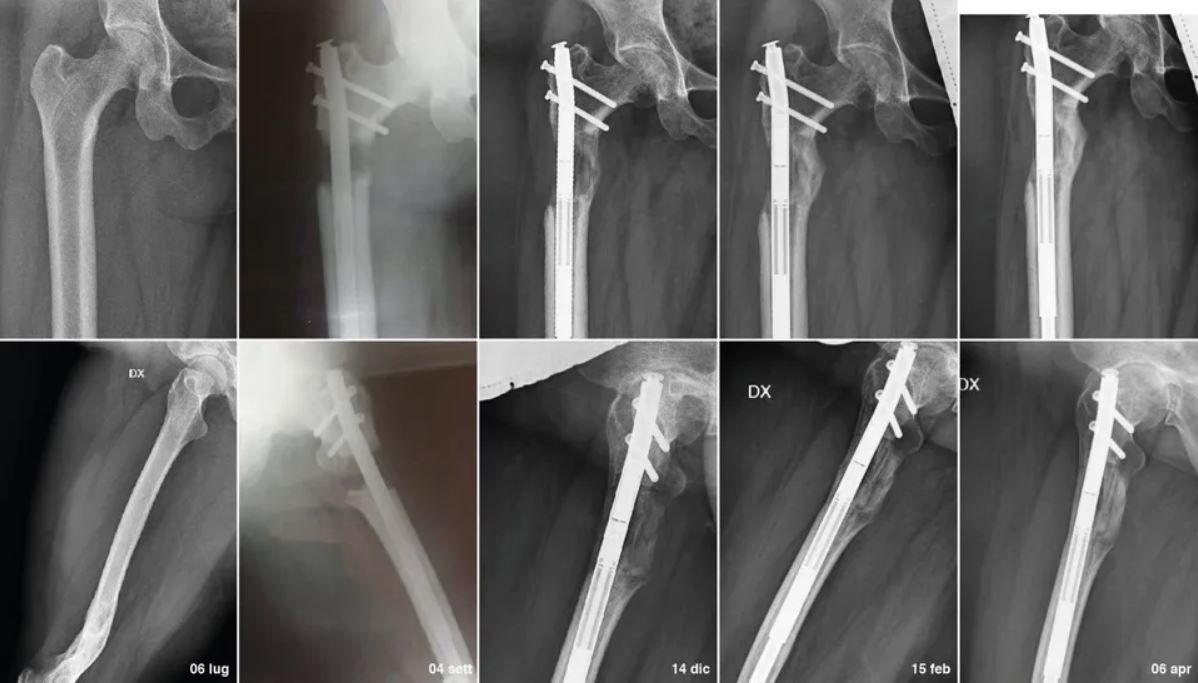

Chiodo Endomidollare e Placche

L'inserimento del chiodo endomidollare o di placche a cielo aperto, viene eseguito dopo uno studio accurato della deformità. In caso di deformità che non richiedono allungamento osseo, queste verranno seguite con controllo postoperatori seriati ogni mese dopo l'intervento, fino a consolidazione ossea raggiunta.